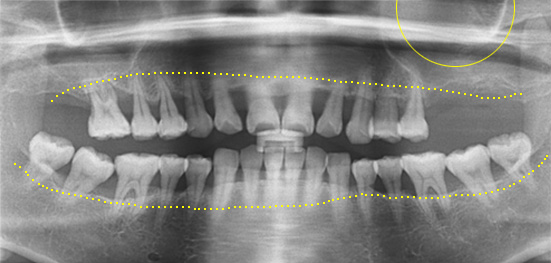

치아가 빠진 후 장시간 방치하면 뼈의 흡수가 진행되어 잇몸 뼈가 약해지게 됩니다. 약해진 잇몸 뼈는 임플란트 식립이 어려워 부족한 뼈를 보강한 후 임플란트 시술을 해야 합니다.

약한 잇몸 뼈는 임플란트 시술 후 부작용을 야기 시킬 수 있어 다양한 방법(골이식술, 골유도재생술, 골신장술 등)으로 뼈를 재생시켜야 튼튼한 임플란트 시술이 가능합니다.